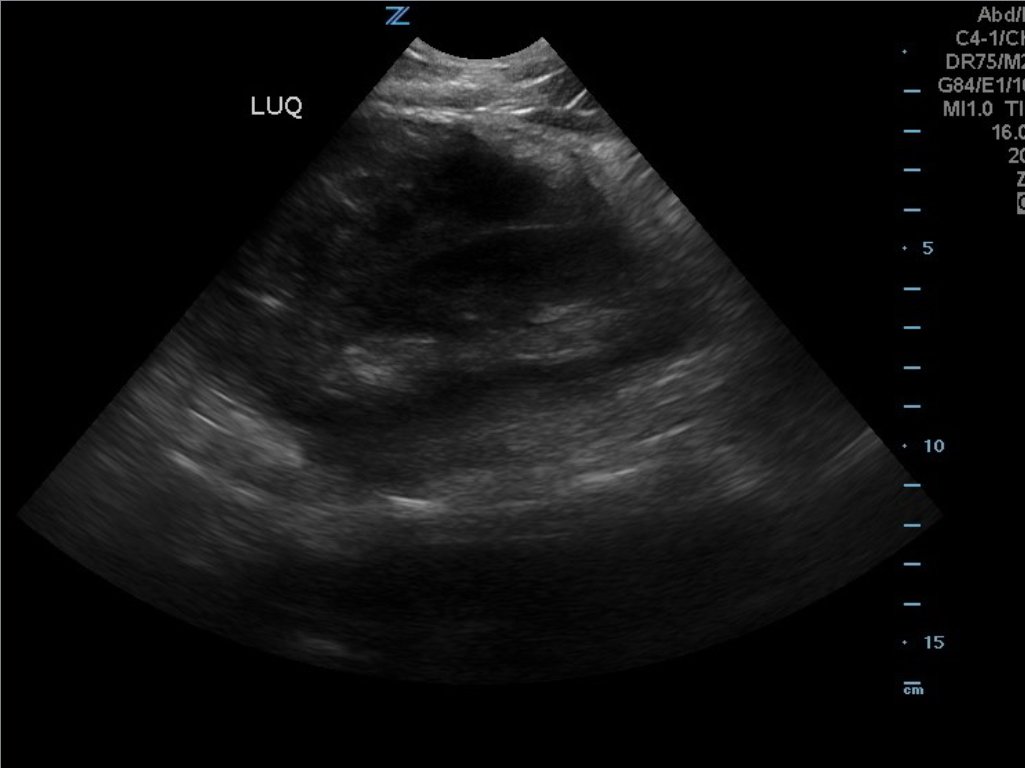

FAST Exam to Diagnose Subcapsular Renal Hematoma

A 49-year-old male presents for evaluation of hematuria and left flank pain after mechanical fall down stairs four days ago. Point-of-care ultrasound (POCUS) focused assessment with sonography in trauma (FAST) exam demonstrated subcapsular renal hematoma. Once a subcapsular hematoma is recognized the provider should keep in mind that this condition may be managed conservatively in patients with two normally functioning kidneys, but may require urgent intervention if the patient is at risk for significant renal disease, such as a single kidney. The use of bedside ultrasound can expedite diagnosis and care for these patients, and allow proper consultants to be contacted early. Some consultants that may need to be consulted include nephrology, urology, and/or internal medicine. This case report emphasizes the utility of the FAST exam for patients presenting for non-acute trauma. The FAST exam can be utilized not only to identify free fluid in the abdomen and pelvis but also to visualize organs and the surrounding tissues for abnormalities after a trauma.